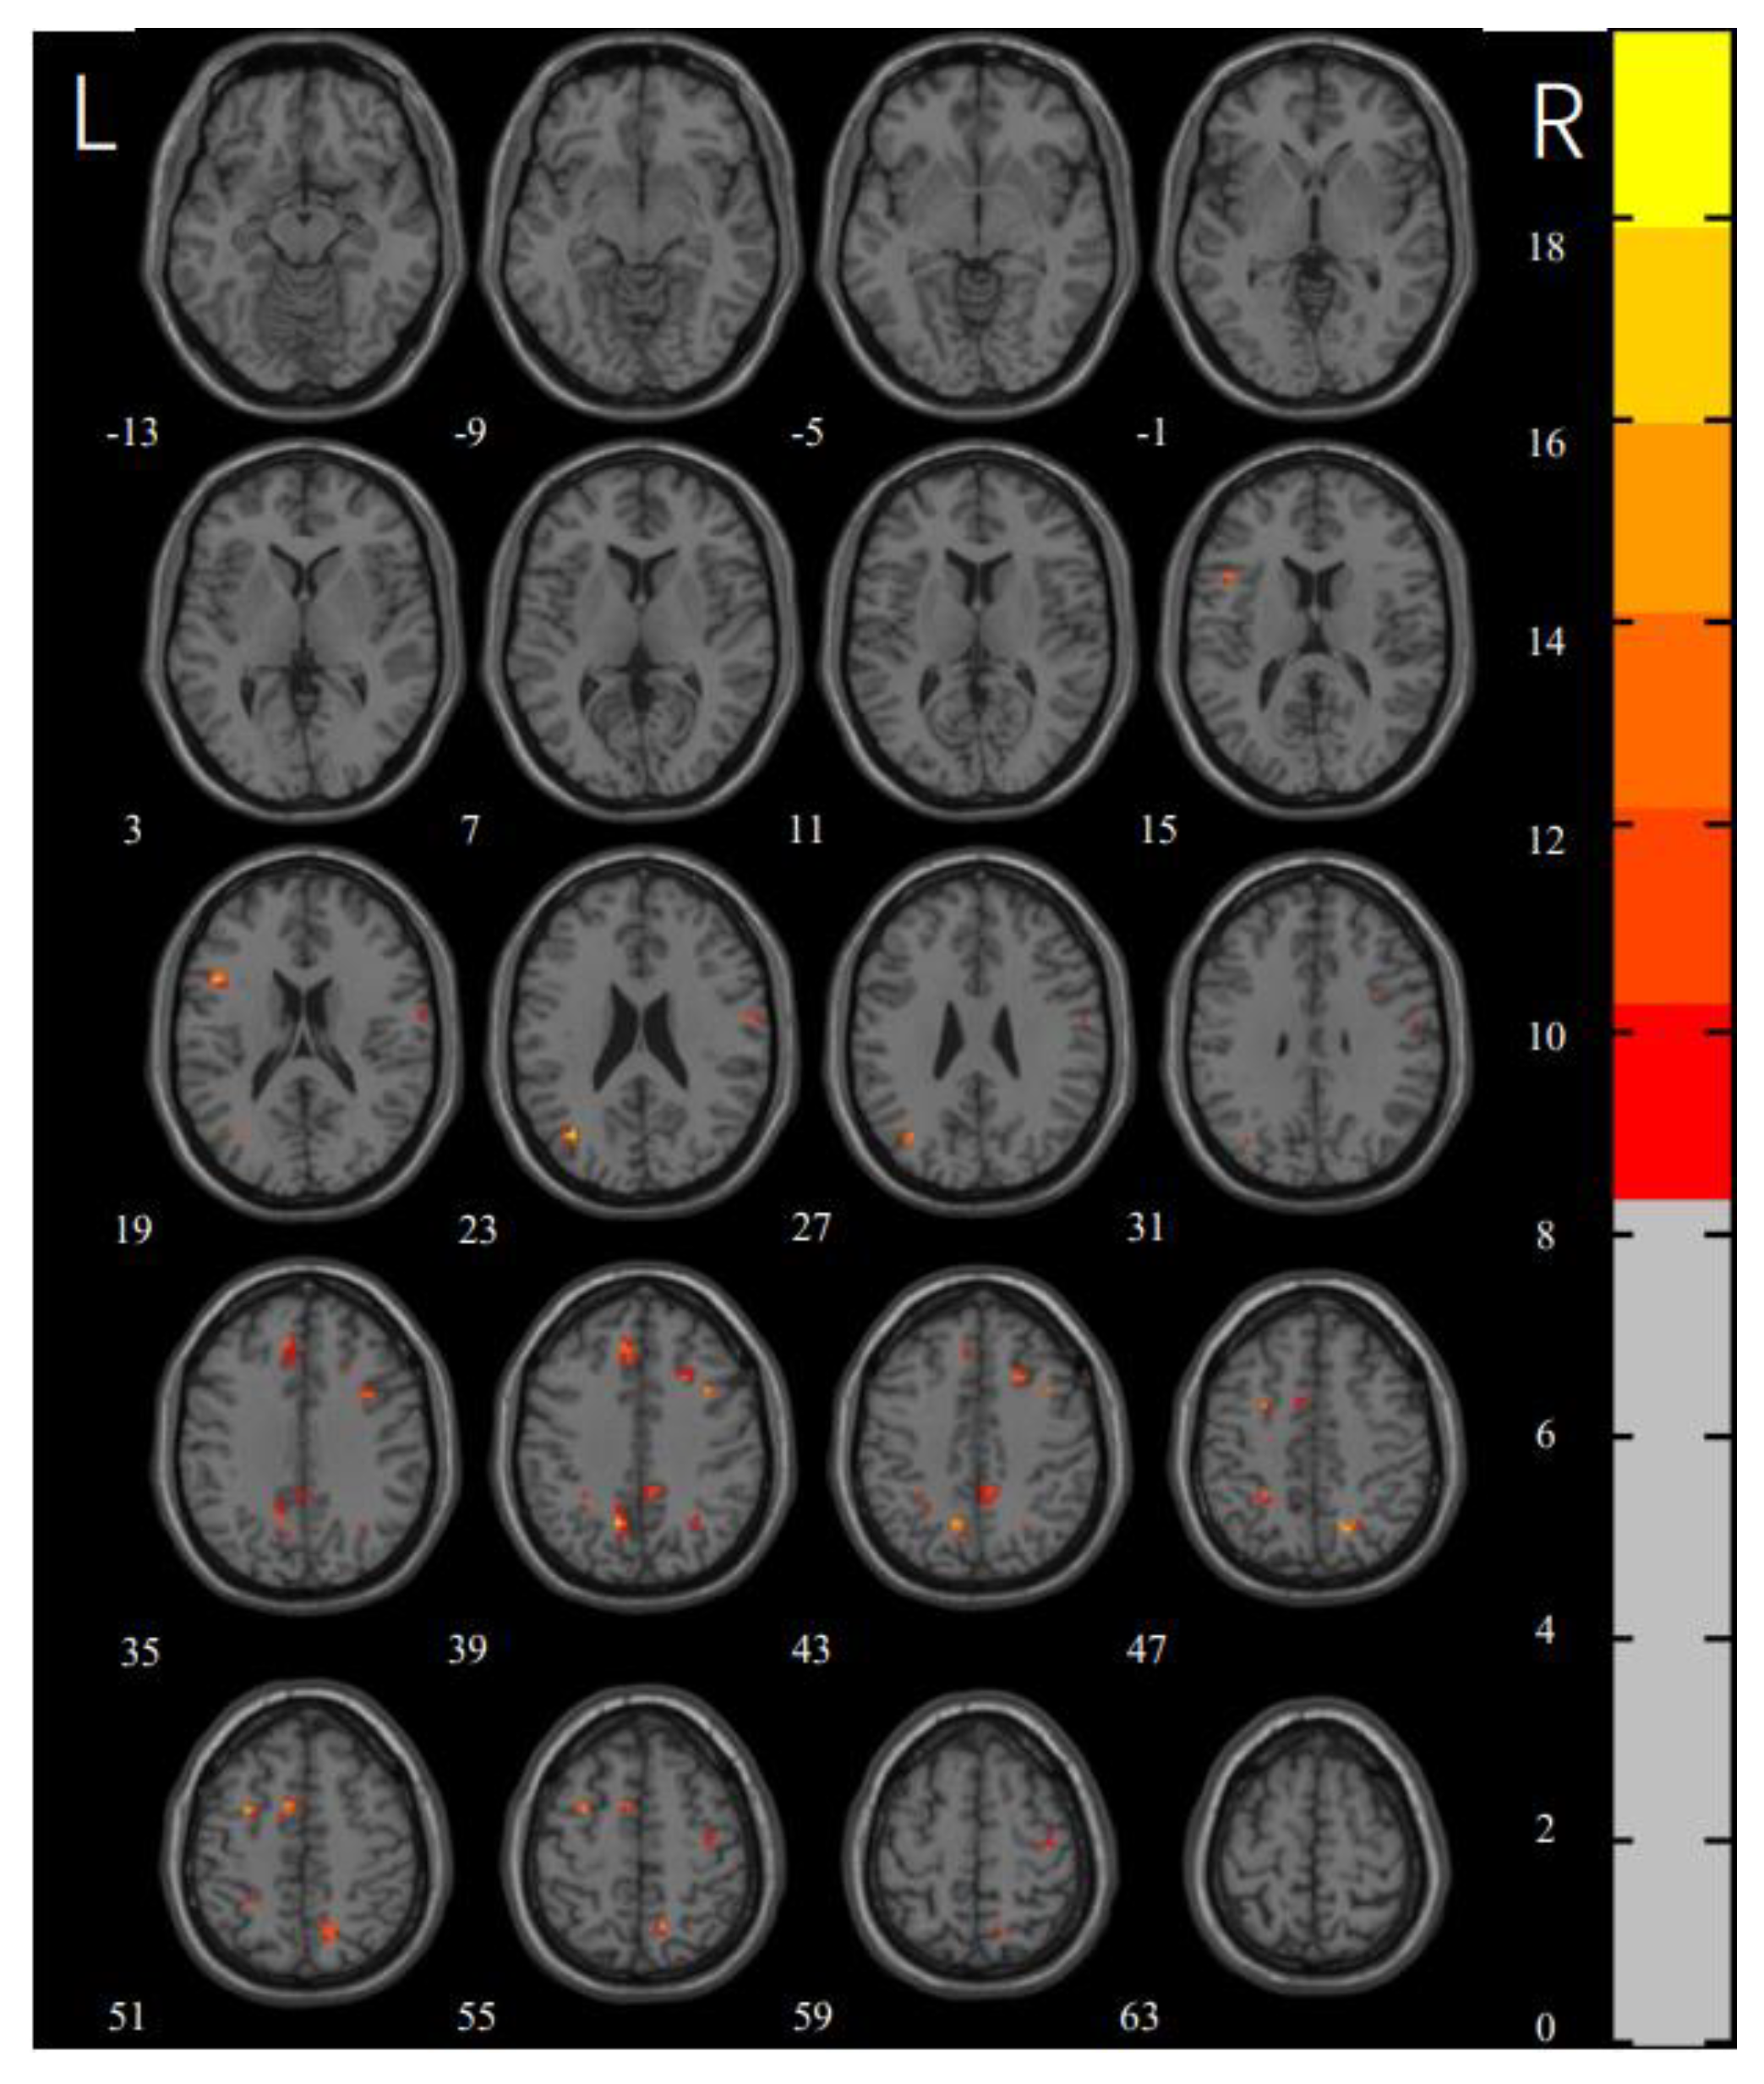

3.2. ReHo

| MNI x, y, z | Voxels | F | Side | Brain Region | |

|---|---|---|---|---|---|

| CL1 | −48, 15, 18 | 12 | 17.3371 | L | inferior frontal gyrus |

| CL2 | −36, −69, 24 | 14 | 19.83114 | L | middle occipital gyrus |

| CL3 | 60, −6, 21 | 11 | 10.8797 | R | postcentral gyrus |

| CL4 | 36, 12, 39 | 10 | 14.4576 | R | middle frontal gyrus |

| CL5 | 18, −63, 48 | 17 | 16.4027 | R | precuneus |

| CL6 | −9, 36, 39 | 22 | 12.6563 | L | medial superior frontal gyrus |

| CL7 | −12, −60, 39 | 24 | 18.7764 | L | precuneus |

| CL8 | 21, 18, 42 | 11 | 13.9385 | R | superior frontal gyrus |

| CL9 | −27, −45, 48 | 12 | 13.076 | L | inferior parietal gyrus |

| CL10 | −30, 3, 51 | 11 | 16.1396 | L | middle frontal gyrus |

| CL11 | −9, 6, 51 | 13 | 14.7148 | L | supplementary motor area |

| CL12 | 39, −12, 57 | 11 | 11.5019 | R | precentral gyrus |